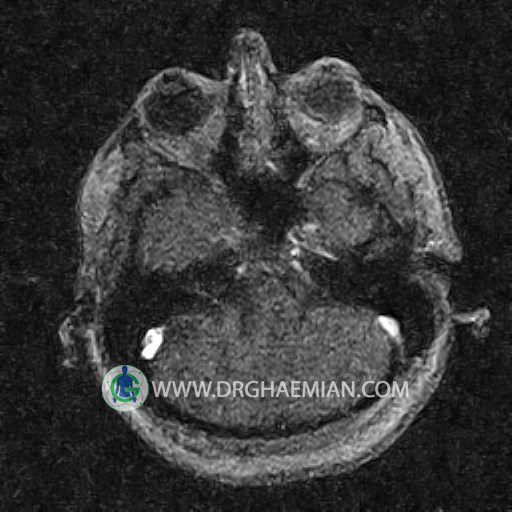

ام آر وی یک روش تصویربرداری دقیق و غیر تهاجمی است که برای معاینه ورید های بدن و ارزیابی سلامت رگ ها استفاده می شود. ورید ها خون را از اعضای بدن به قلب باز می گرداند تا دوباره اکسیژن و مواد مغذی به خون داده شود. ام آر وی جریان خون را ارزیابی و موارد غیرعادی مضر مانند لخته های خونی را شناسایی می کند. در این کیس ترومبوز دیواری مغز در سینوس عرضی راست و ترمبوز جزئی در سینوس عرضی چپ دیده می شود.

Technique: TOF ( time of flight ).

The great cerebral vein Galen inferior sagittal , straight sinus and left sigmoid sinus appear normal.

The right sigmoid sinus present a normal caliber.

– Narrowing of left transverse sinus with filling defect & inthimal irregularity

suggestive for partial thrombosis

– Inthimal irregularity in anterior wall of right transverse sinus suggestive for mural thrombosis

are seen